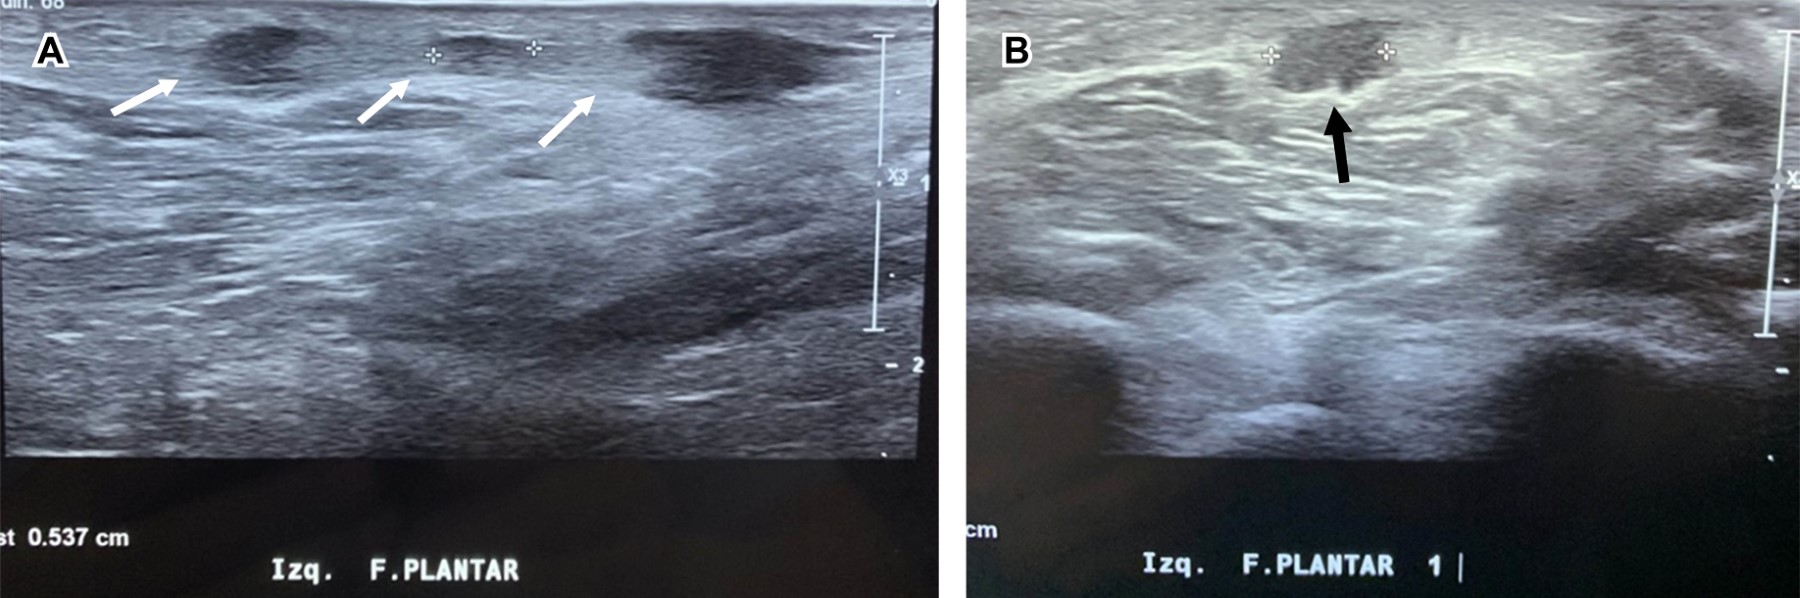

Femenino de 56 años, con índice de masa corporal de 21; practicante de pilates desde hace 10 años, acude por haber palpado en región plantar izquierda presencia de masa de 1 cm de diámetro; a la exploración dirigida: marcha normal, a la palpación tres nódulos palpables, no desplazables sobre planos profundos, discretamente dolorosas a la presión, de tamaños distintos (el mayor de 1 cm de diámetro y los otros dos de 0.5 cm). El mayor se encuentra localizado a la altura del escafoides. Con la sospecha clínica de fibromatosis plantar se efectúa ultrasonido, confirmando diagnóstico (Figura 1). Se derivó a rehabilitación, aplicando termoterapia y estiramiento de la fascia plantar; a tres meses de evolución, el nódulo mayor disminuyó a 0.5 cm de diámetro, no siendo palpables los dos más pequeños descritos al inicio.

Figura 1